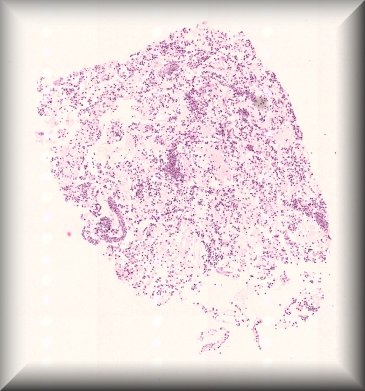

Hind M. Alkatan (Guest): A 10-month-old boy presented with a painless scrotal mass.External examination demonstrated left scrotal non-tender hard mass measuring 4x3 cm in size, with negative transillumination test. Ultrasonography of left scrotum showed a well-circumscribed, oval shaped mass with mixed echogenicity, The mass contained both cystic and solid component, with no clear visualization of the left testicle.The patient underwent left scrotal exploration with high inguinal orchidectomy |